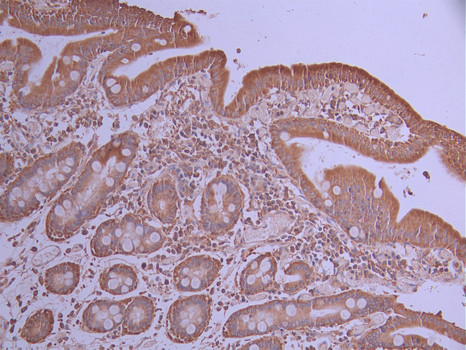

IHC image of CSB-RA786302A0HU diluted at 1:100 and staining in paraffin-embedded human small intestine tissue performed on a Leica BondTM system. After dewaxing and hydration, antigen retrieval was mediated by high pressure in a citrate buffer (pH 6.0). Section was blocked with 10% normal goat serum 30min at RT. Then primary antibody (1% BSA) was incubated at 4°C overnight. The primary is detected by a Goat anti-rabbit polymer IgG labeled by HRP and visualized using 0.05% DAB.